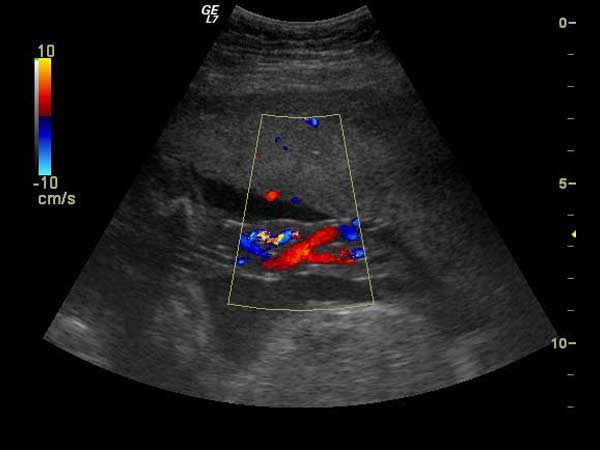

Om te weten of een paard voldoende in conditie is voor de gevraagde prestaties, voert EquiSound melkzuurbepalingen uit. Ook inspanningstesten met Holter monitoring om de hartfrequentie te controleren wanneer het paard werkt behoren tot de mogelijkheid. Op basis van deze onderzoeken kan het trainingsschema geoptimaliseerd worden. Echocardiografie met Doppler is aangewezen indien er tekenen zijn die op hartziekten wijzen en die verder onderzocht moeten worden.